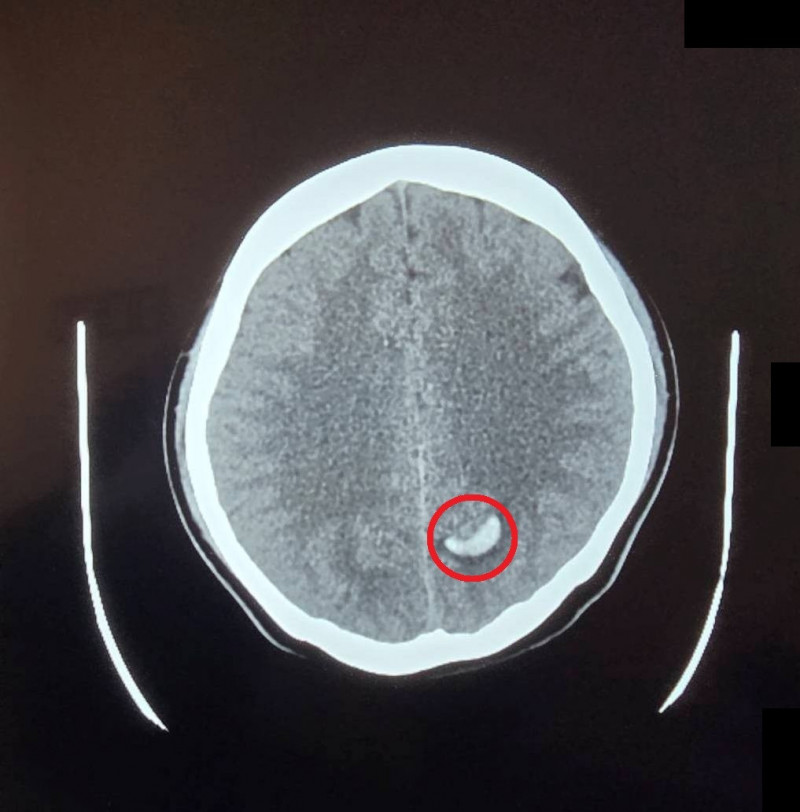

〔記者張勳騰/苗栗報導〕23歲的周小姐正值青春年華,日前卻在毫無預兆頭部劇疼痛,隨即出現嚴重的頭暈與嘔吐感,家屬見狀趕緊將她送往苗栗市大千醫院急診。經腦部電腦斷層掃描,醫師赫然發現其左側腦部有出血跡象,且出血位置極其不尋常。醫療團隊隨即展開精密檢查,證實為罕見的「顱內動靜脈畸形」引發出血。所幸進行微創血管內栓塞治療後,順利止住出血,病人症狀明顯改善,成功化解一場腦內危機。

大千醫院神經放射科醫師康靜維指出,「顱內動靜脈畸形」是一種先天性的腦血管病變。在胚胎發育過程中,若動脈與靜脈之間缺乏微血管緩衝,導致高壓的動脈血流直接衝入脆弱的靜脈,管壁便會因長期無法負荷壓力而逐漸薄弱,最終像吹太大的氣球一樣破裂,引發腦出血。這種疾病好發於30歲左右的年輕族群,臨床表現以腦出血最為常見,但也可能出現癲癇或長期慢性頭痛等症狀。